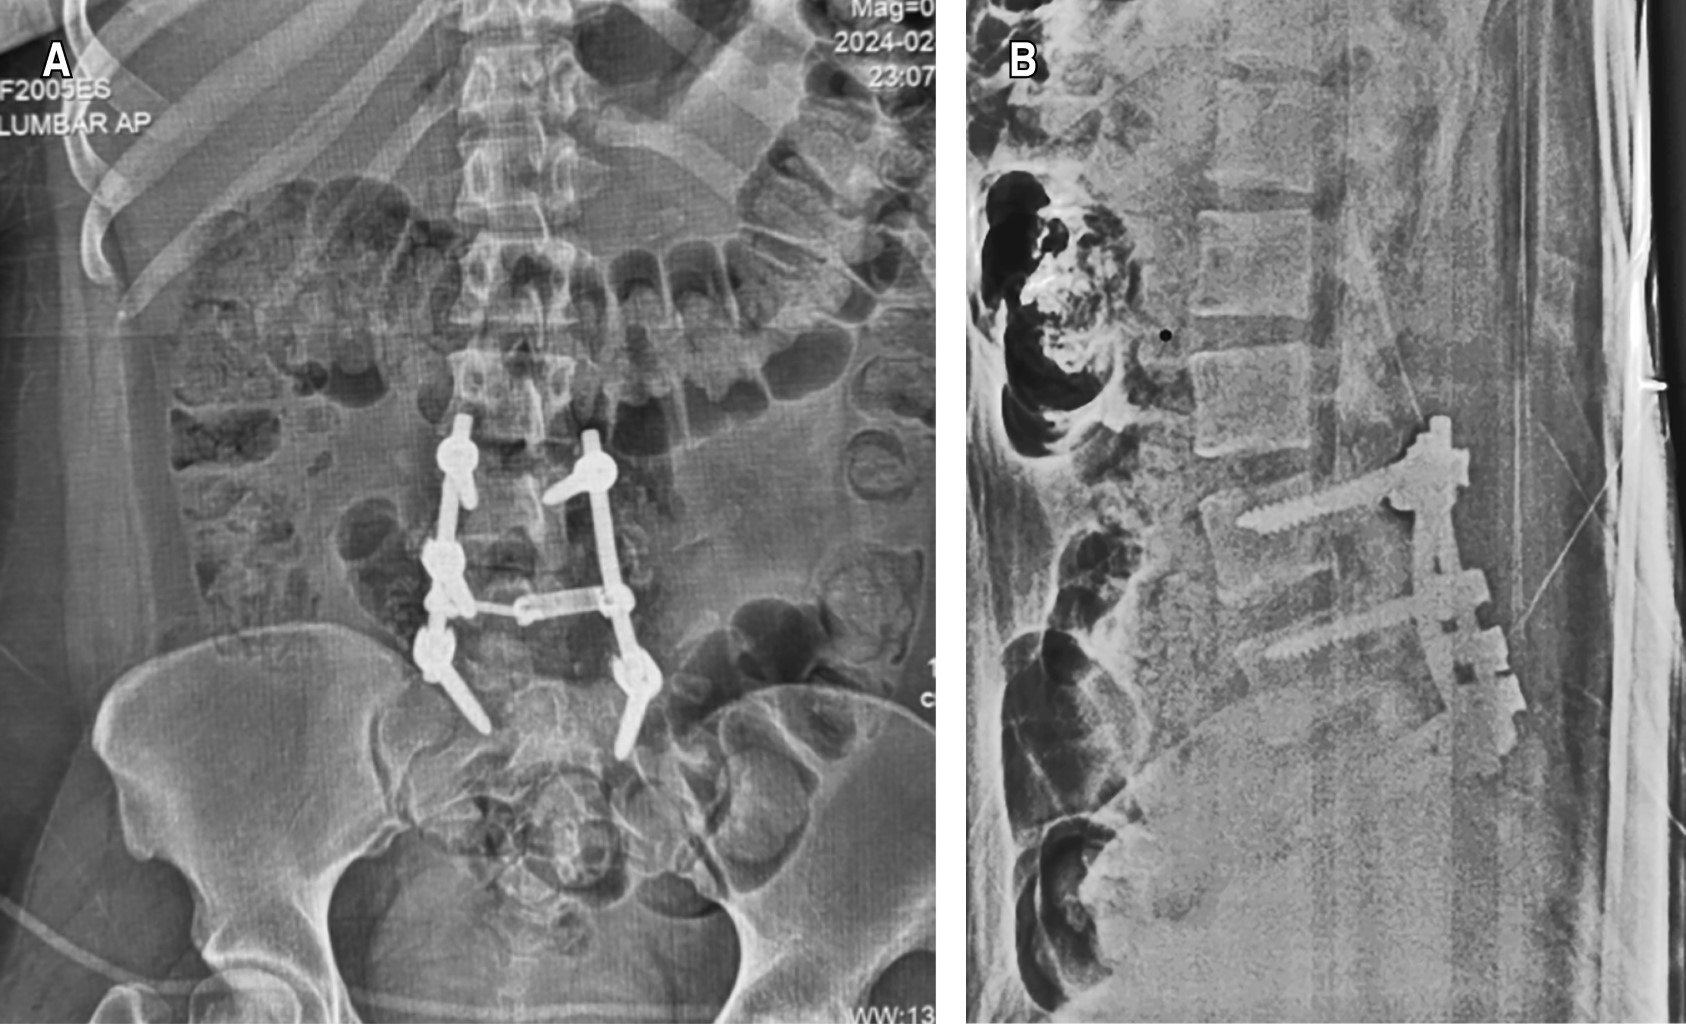

De manera inicial, mediante fluoroscopio, se realiza instrumentación transpedicular bajo referencias anatómicas (línea que converge proceso transverso y borde lateral de articulación facetaria sobre proceso mamilar); con disección ortogonal a proceso espinoso e inserción a 30° medial en plano axial, se colocan dos tornillos en L4, dos tornillos en L5 y dos tornillos en S1, con necesidad de efectuar facetectomía parcial L4-L5 derecha para realizar distracción y reducción paulatina de luxación, Se cierra sistema con candados y barras previamente moldeados (Figura 4).

Se practica control radiográfico inmediato posterior a la cirugía. Se encuentra falta de reducción de la luxación (Figura 5) con fijación parcial de tornillos transpediculares; sin embargo, la paciente muestra evidente mejoría clínica, encontrando dentro de las primeras 24 horas postoperatorias cambios respecto a la exploración física inicial, con fuerza muscular en ambas extremidades inferiores 5/5 en escala de Daniels, con adecuada diferenciación en pruebas de pica y toca hasta el dermatomo L5 donde presenta hipoestesia de la zona de pierna y dorso del pie izquierdo.